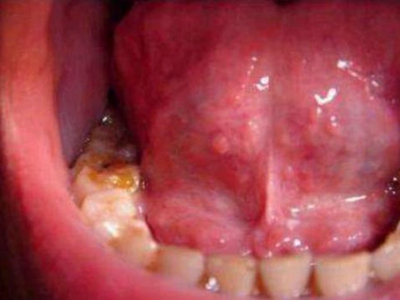

口腔尖锐湿疣是由人乳头瘤病毒感染引起的发生于口腔黏膜的性传播疾病,主要由HPV6、11等型引起。引起尖锐湿疣的某些HPV亚型与癌的发生有关,表现为疣状结节。口腔尖锐湿疣多由口交感染引起,好发生于性活跃的青、中年。

口腔尖锐湿疣好发于舌、牙龈、腭等部位,表现为单个或多个无痛性的疣状结节,有蒂或无蒂,可逐渐增大或融合,形成菜花状、乳头状赘生物,颜色呈肉色或苍白色,患者可有异物感。